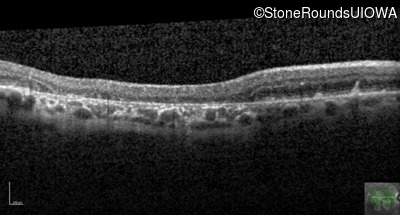

Optical Coherence Tomography - Right - 20/25

Exemplar / OCT Stack

Optical Coherence Tomography - Left - 20/25 -2